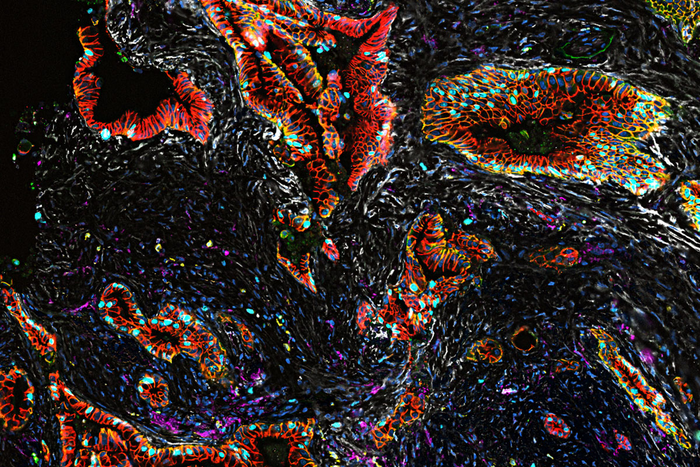

The researchers conducted a deep analysis of the genetics and protein manufacturing of 83 pancreatic tumor samples donated by 31 patients who participated in the study. They noted how the tumors differed across the volume of the tumor and at various times as the patients underwent treatment.

Ding, Fields and their colleagues, including fellow co-senior author David G. DeNardo, PhD, a professor of medicine, mapped out two key transition points in the development of pancreatic cancer. One involves the shift normal pancreatic cells make as they become precancerous. And the second transition point involves the shift from precancerous cells to early cancer cells. Future studies will focus on a third key transition point: that of the original tumor shifting to metastatic disease, which spreads to other parts of the body.